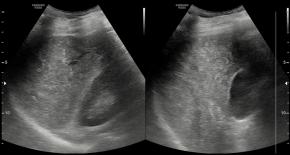

Comments Although the hepatic parenchyma may initially appear coarse, the liver actually shows numerous tiny hyperechoic foci with comet-tail artifacts scattered throughout the parenchyma. In addition, there are no accompanying findings suggestive of chronic liver disease or cirrhosis, such as liver contour blunting, surface nodularity, liver volume redistribution, dilatation of the portal vein, or splenomegaly.

• Multiple tiny low-attenuating lesions are scattered throughout the hepatic parenchyma, which is a characteristic CT finding of biliary hamartomatosis.